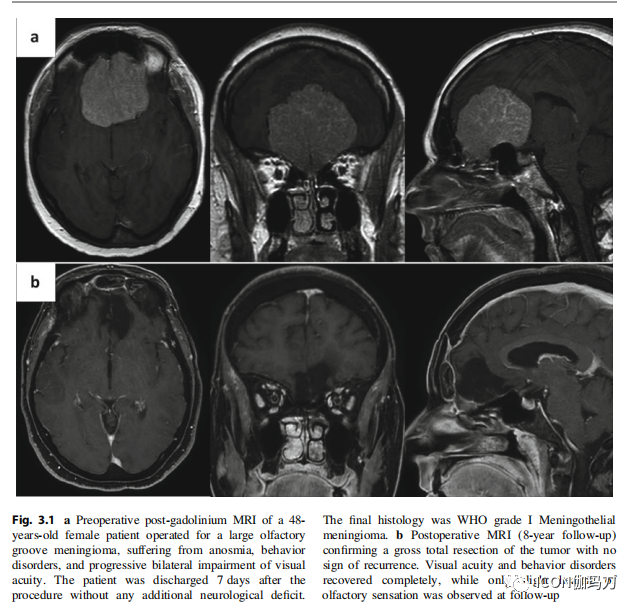

图3.1 a伴有嗅觉缺失、行为障碍和进行性双侧视力损害的48岁女性患者,手术切除大的嗅沟脑膜瘤。术后7天出院,无其他神经功能障碍。最终组织学为WHO分级I级脑膜上皮性脑膜瘤。b术后MRI(随访8年)证实肿瘤大体全切除,无复发迹象。视力和行为障碍完全恢复,而嗅觉仅轻微好转。